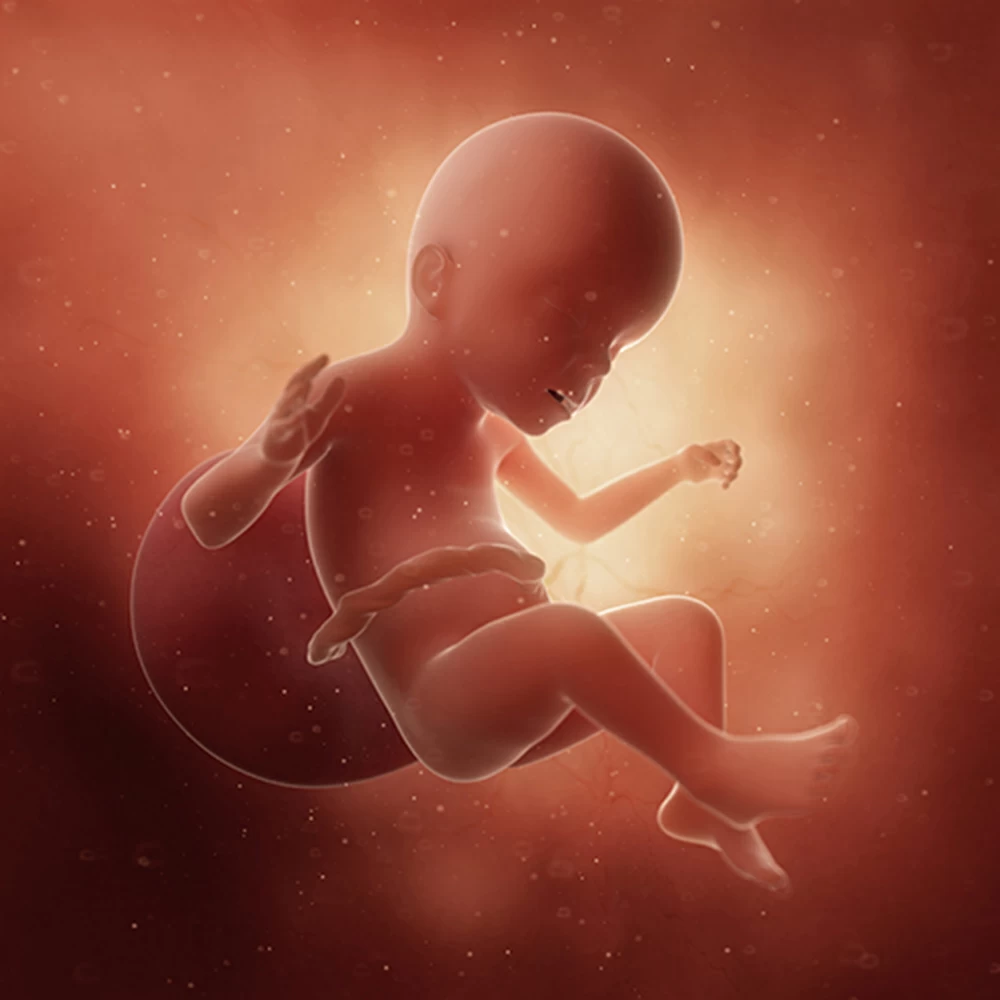

Неделя № 22

На 22 неделе размеры плода увеличиваются до 28 см, вес – до 450-500 грамм. Размеры головки становятся пропорциональны туловищу и конечностям. Ноги практически все время находятся в согнутом состоянии.

Полностью сформирован позвоночник плода: он имеет все позвонки, связки и суставы. Продолжается процесс укрепления костей.

Совершенствуется нервная система плода: головной мозг содержит уже все нервные клетки (нейроны) и имеет массу около 100 грамм. Ребенок начинает интересоваться своим телом: ощупывает свое лицо, руки, ноги, наклоняет голову, подносит пальцы ко рту.